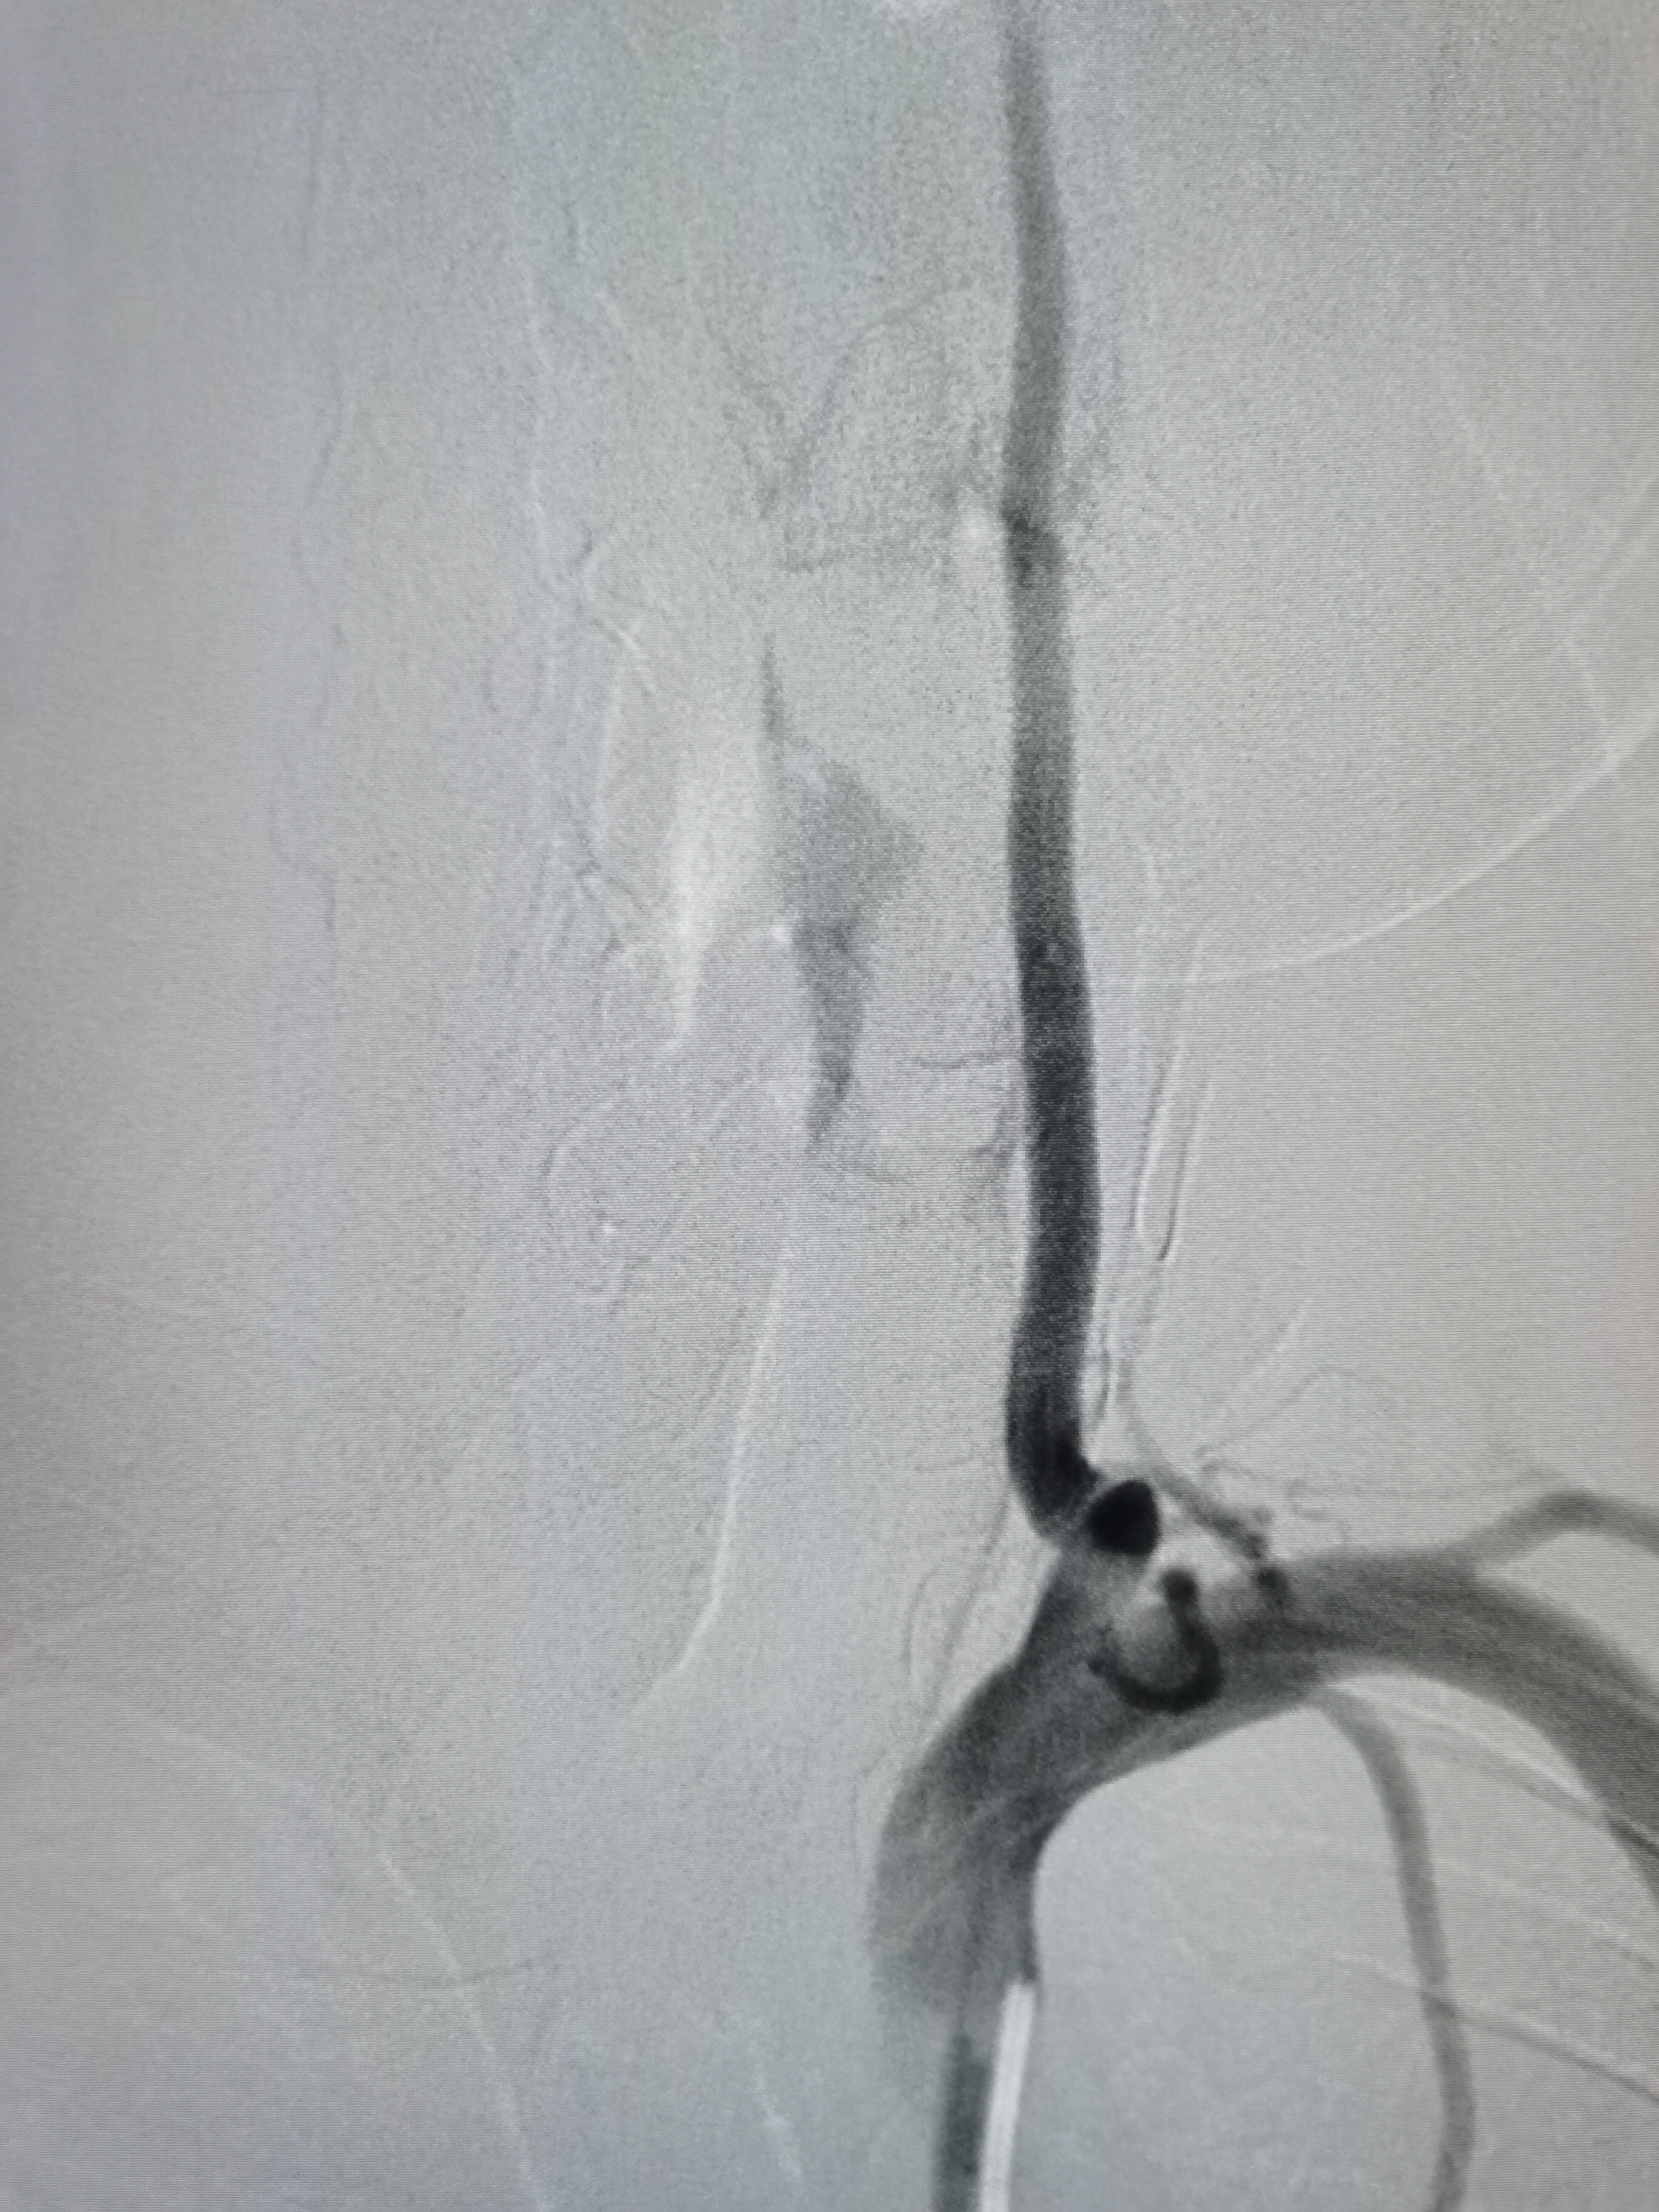

右侧颈内动脉起始部粥样硬化斑块形成。

颅内侧位显影可。